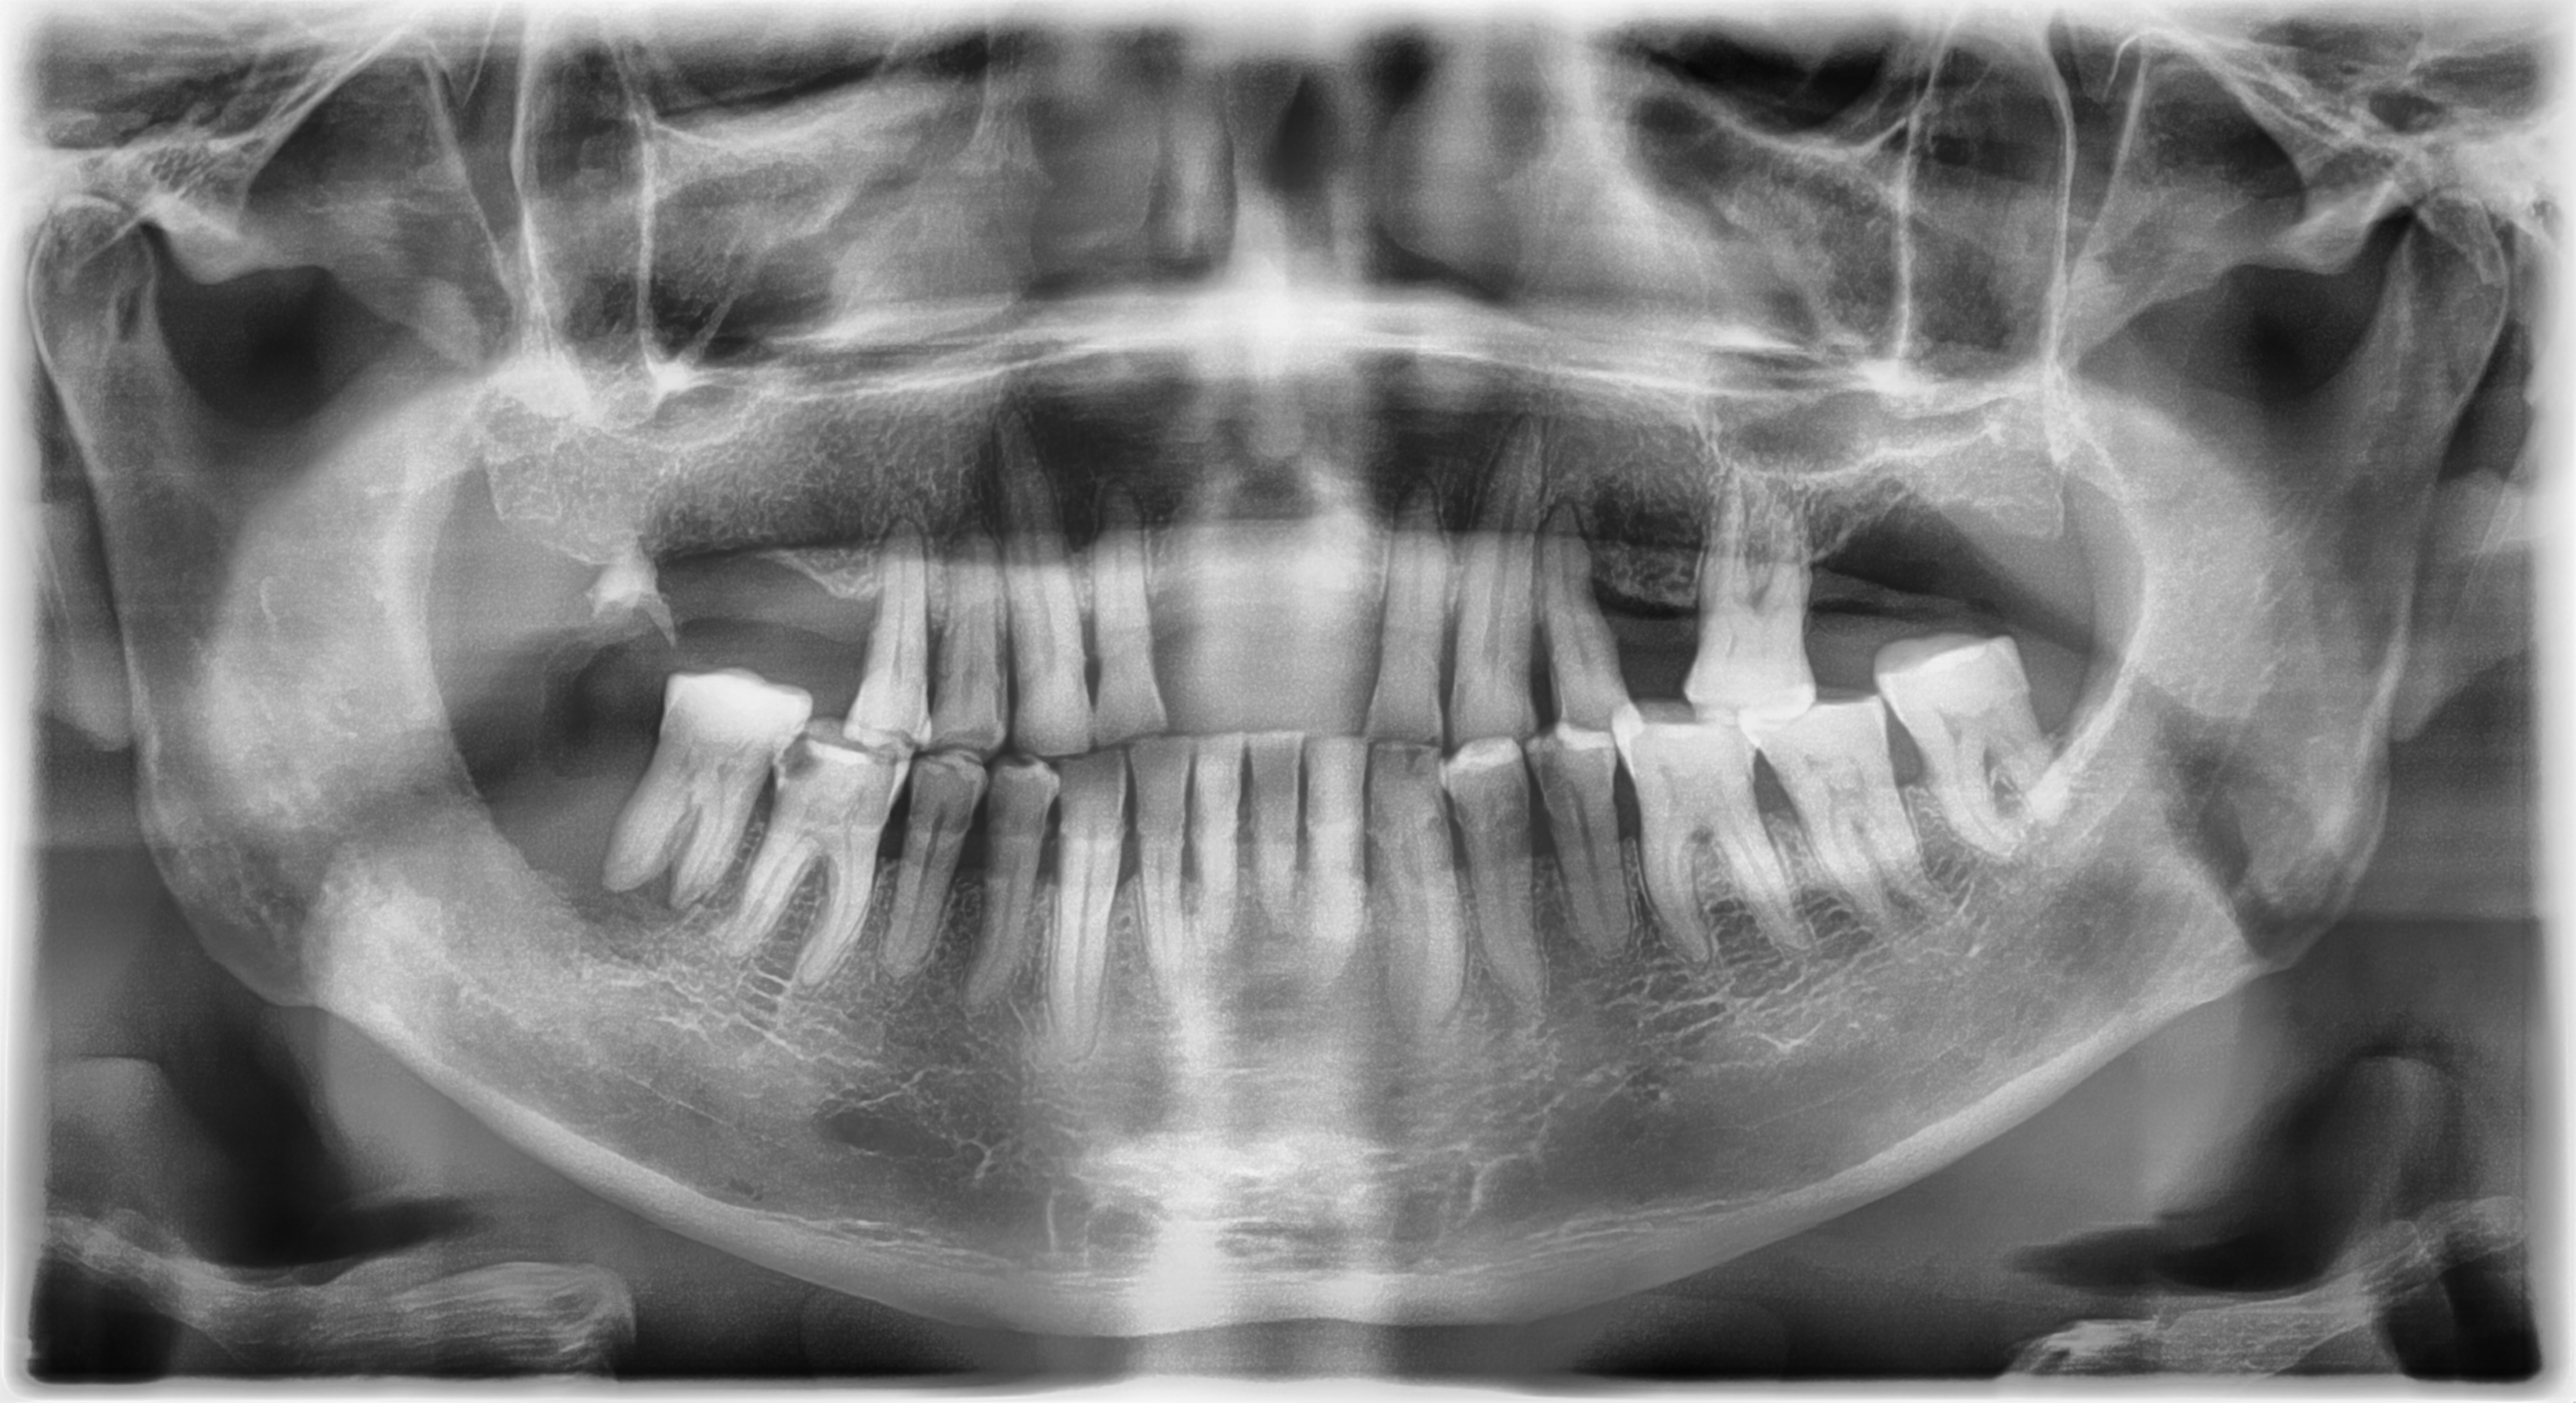

Todos los pacientes deberán de ser revisados en busca de leucoplasias, eritroplasias, aumentos de volumen y úlceras que no cicatricen en más de 15 días. De igual manera es importante solicitar a todos los pacientes una ortopantomografía, con esta podremos ver lesiones en hueso que no se han manifestado clínicamente.

Se presenta un caso de un hombre de 54 años de edad que acude a consulta con facultativo para extracción de un OD 48, en el cual tenía sintomatología dolorosa, en las citas subsecuentes el paciente no presentaba una cicatrización adecuada, por lo que fue medicado y tratado con colutorios durante 6 meses, el paciente acude a consulta de Patología y Medicina Bucal, presentando una lesión intraoral en trígono retromolar, mucosa yugal y pilar amigdalino, la cual es de color rojo, superficie lisa con áreas de úlcera, dolorosa a la palpación, consistencia indurada. (Imagen 1). Radiográficamente se observa una lesión osteolítica de bordes mal definidos en la misma zona (imagen 2). A la palpación de cuello se encontraron 2 adenomegalias en nivel 2ª y 2B, de aproximadamente 2cm, fijas a planos profundos y dolorosas. Previos estudios de laboratorio e historia clínica se toma la biopsia de la lesión. El reporte histopatológico fue de Carcinoma Oral de Células Escamosas variante acatolítico, por lo que el pronóstico es desfavorable al ser una variante de alto grado.